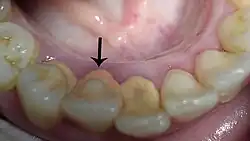

De tandsteen kan ook op of onder de tandvleesrand gaan zitten waardoor het tandvlees ontstoken raakt. Tandsteen is poreuzer dan tandglazuur, waardoor het gemakkelijker verkleurt.

Tandsteen ontstaat doordat calcium en fosfaat uit het speeksel in de tandplak terechtkomen. Die tandplak verhardt. Er zijn twee soorten tandsteen: subgingivaal en supragingivaal. Subgingivaal zit onder het tandvlees, supragingivaal tandsteen zit op de tand of kies. In dat geval kan het verwijderd worden met een zoutstraler.[1]

Tandsteen ontstaat het snelst bij de uitgang van speekselklieren, bijvoorbeeld vlak achter de ondertanden.